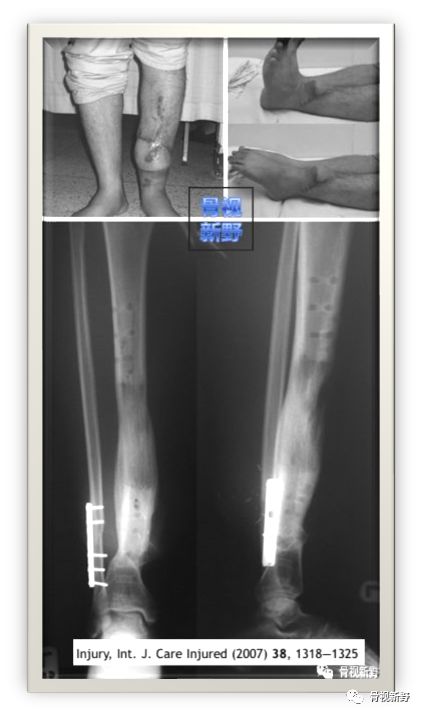

2003年,Rene K.Marti团队再次报道了将AO标准钢板作为外固定架用于开放性骨折以及骨感染性骨不连的固定病例31例,也取得了较好的疗效。

Cases